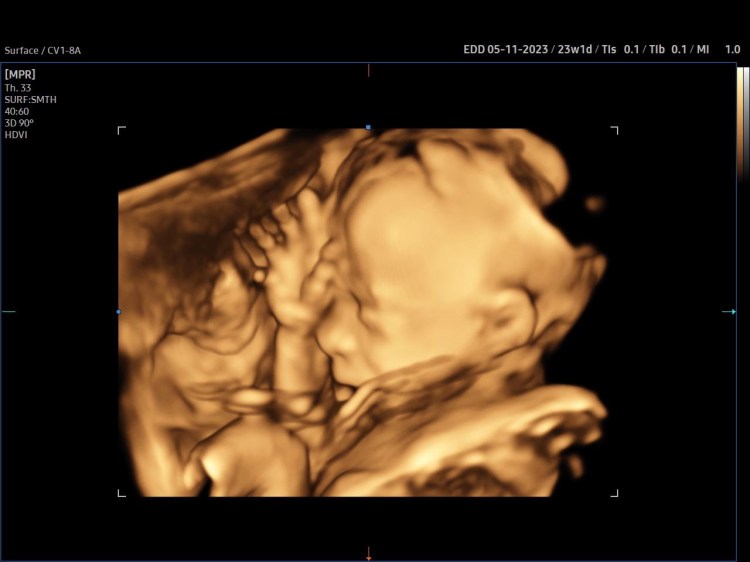

It’s a new year, a new day, and I have a new baby on the way!

Between Covid-19 and winter I didn’t get out as much with my newborn in 2020. I’m hoping this time around, since the “stork” is making the delivery on May 11th, I get to do more hiking with my new baby and my toddler.

I’m excited that we’re having a little girl this time. Don’t get me wrong, my little boy is awesome! It will just be nice to have some back up in the house that doesn’t run on four legs.